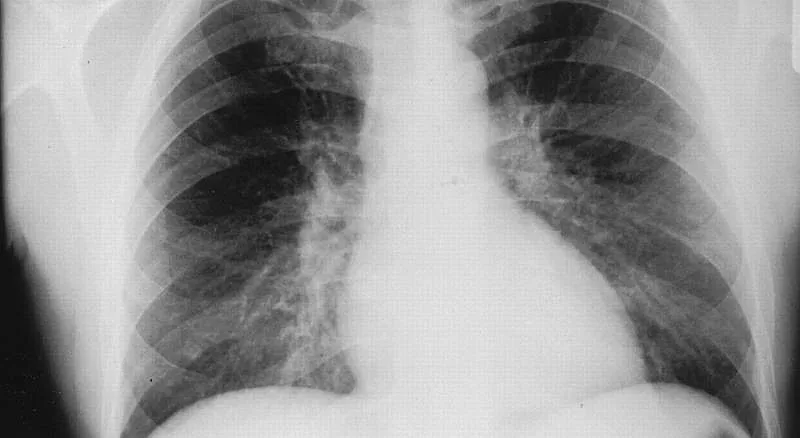

Механизмът на предаване на инфекцията при човека се реализира главно аерозолно и по-рядко алиментарно или чрез ухапване от заразени кърлежи. Поради неизяснените все още факти относно характера на епидемичния процес (единични случаи, спорадични взривове или епидемии с различен интензитет), сходната клинична картина с други заболявания, което затруднява ранното диагностициране и възможностите за хронифициране, интересът към заболяването непрекъснато нараства.